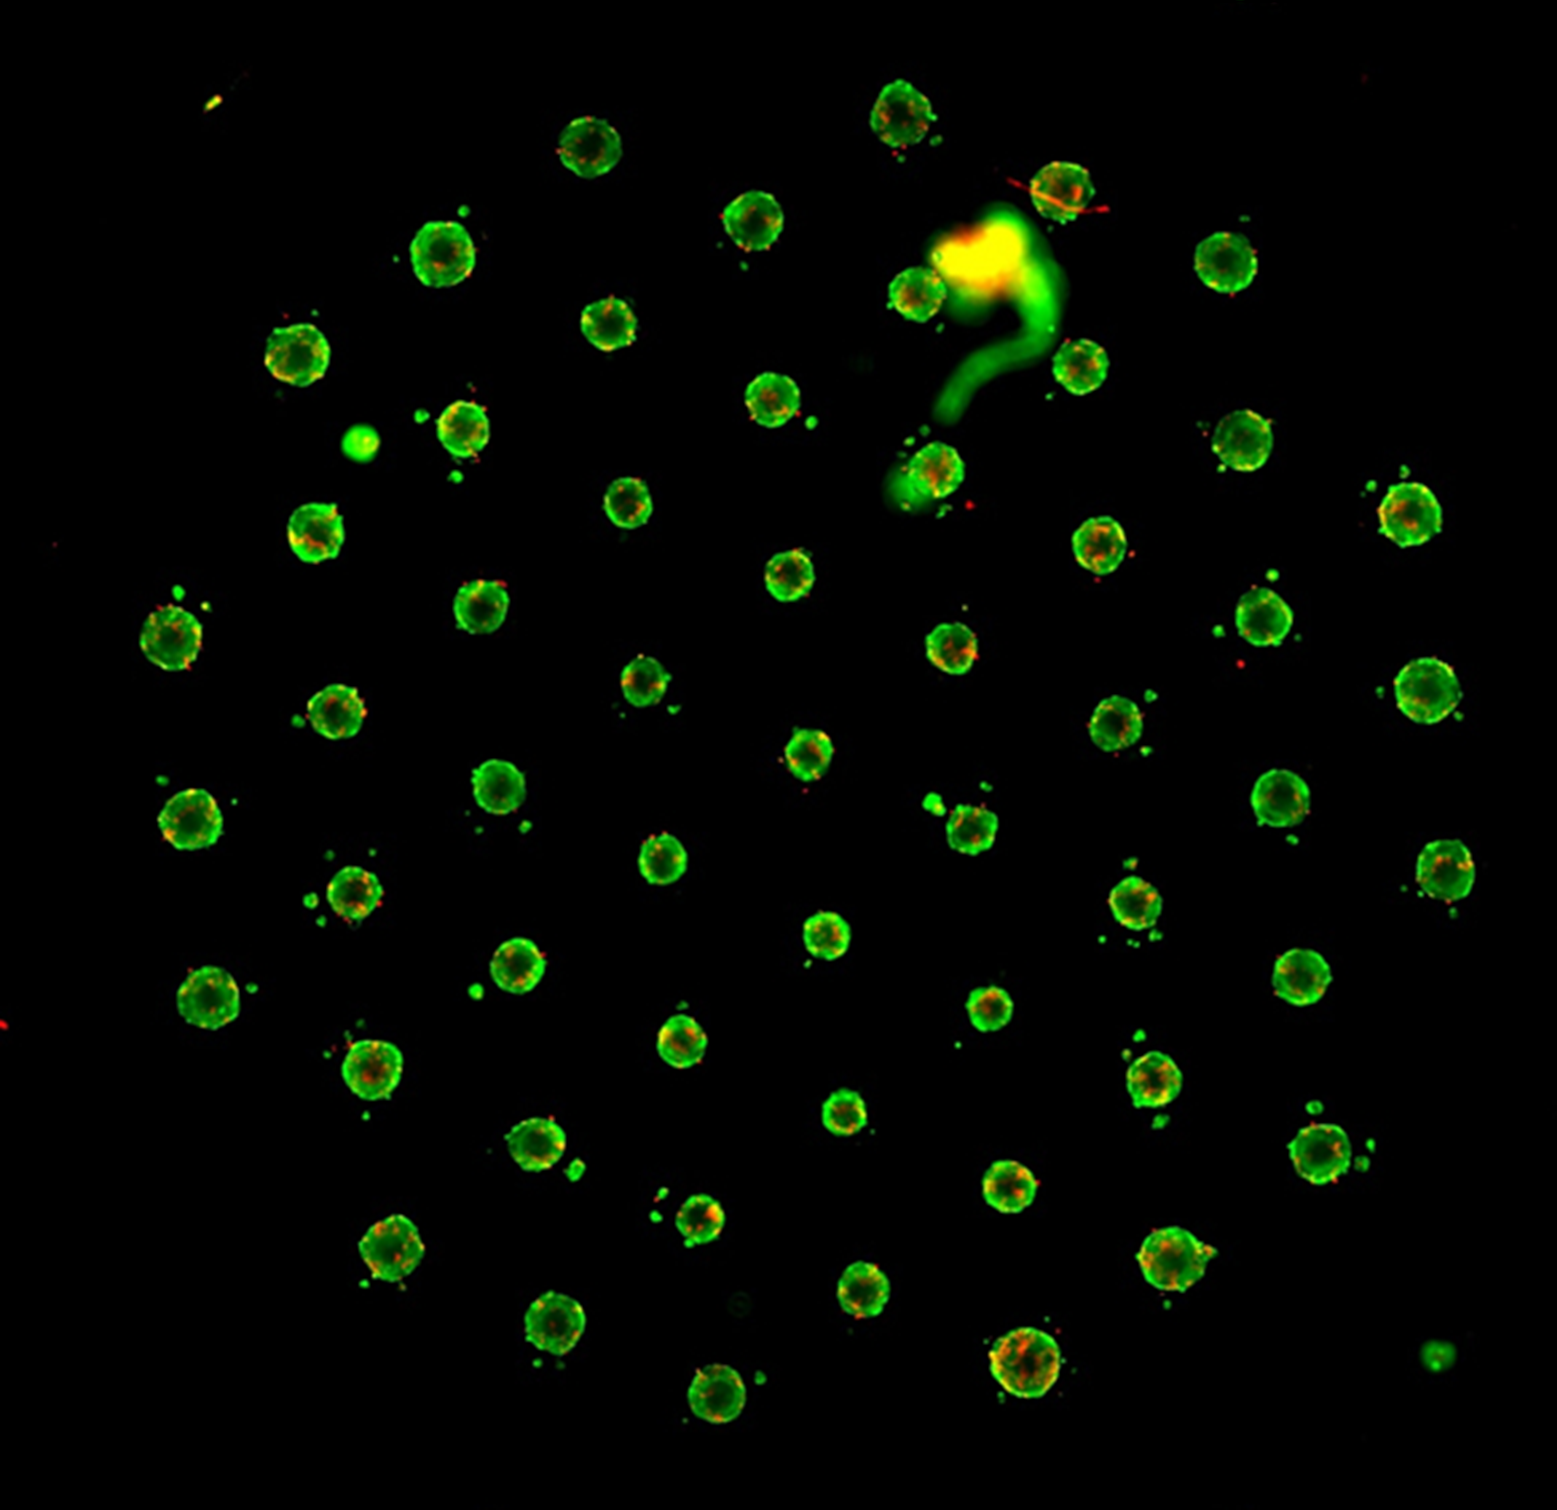

Reproducible and uniform organoids

Our HepatoPlates (PDMS free) ensure precise location of organoids in the well to support consistent and reproducible HCS imaging.

Up to 55 organoids per well for immediate high content screening (HCS) and -Omics in drug discovery